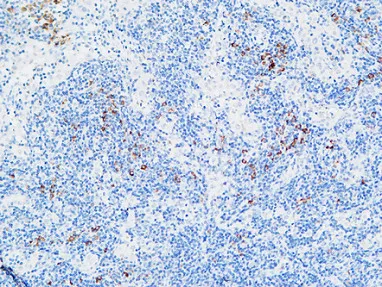

MPO Rabbit Polyclonal Antibody

Cat: APRab14056

Size1:50μl Price1:$118

Size2:100μl Price2:$220

Size3:500μl Price3:$980

Size2:100μl Price2:$220

Size3:500μl Price3:$980